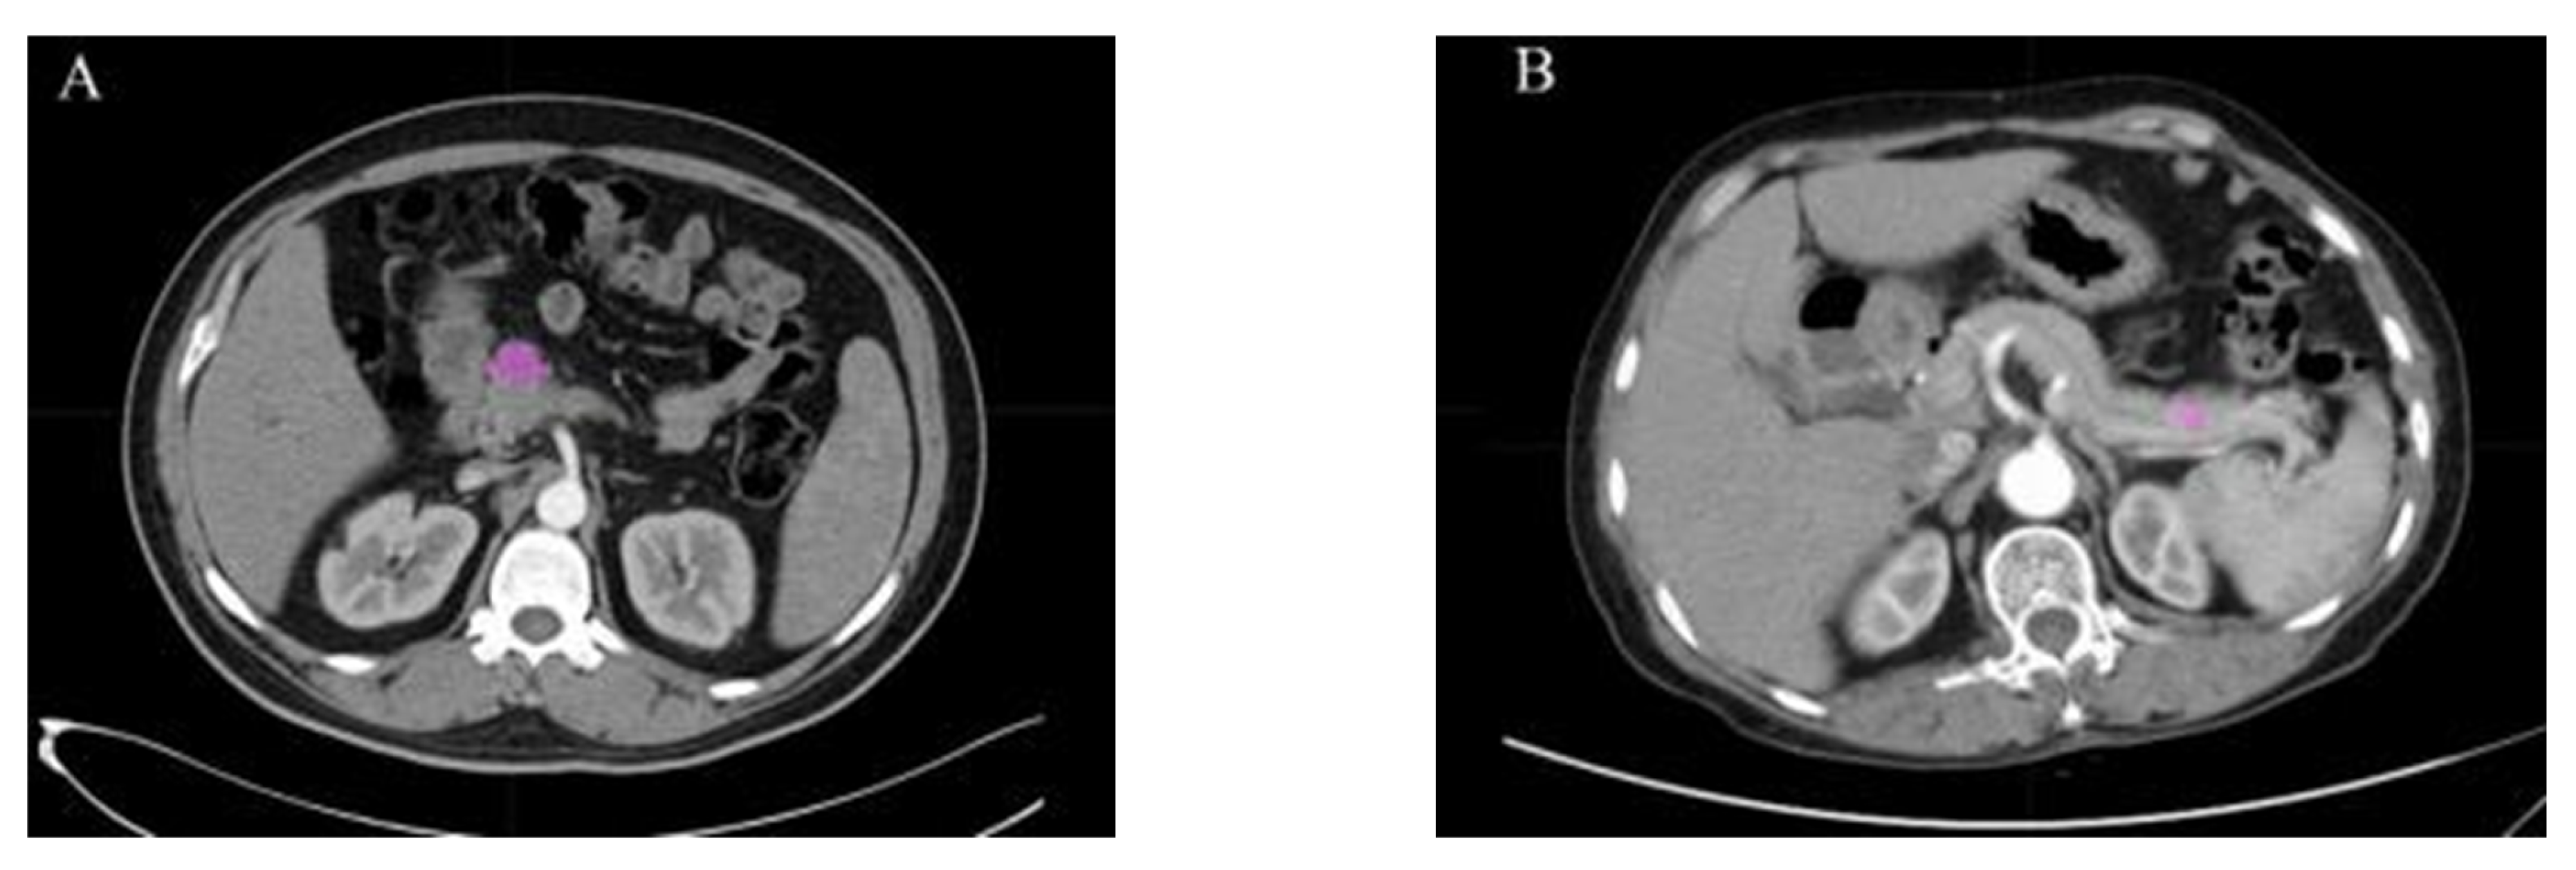

- Javed, S.; Qureshi, T.A.; Gaddam, S.; Wang, L.; Azab, L.; Wachsman, A.M.; Chen, W.; Asadpour, V.; Jeon, C.Y.; Wu, B.; et al. Risk Prediction of Pancreatic Cancer Using AI Analysis of Pancreatic Subregions in Computed Tomography Images. Front. Oncol. 2022, 12, 1007990. [Google Scholar] [CrossRef]

- Qureshi, T.A.; Gaddam, S.; Wachsman, A.M.; Wang, L.; Azab, L.; Asadpour, V.; Chen, W.; Xie, Y.; Wu, B.; Pandol, S.J.; et al. Predicting Pancreatic Ductal Adenocarcinoma Using Artificial Intelligence Analysis of Pre-Diagnostic Computed Tomography Images. Cancer Biomark. 2022, 33, 211–217. [Google Scholar] [CrossRef]